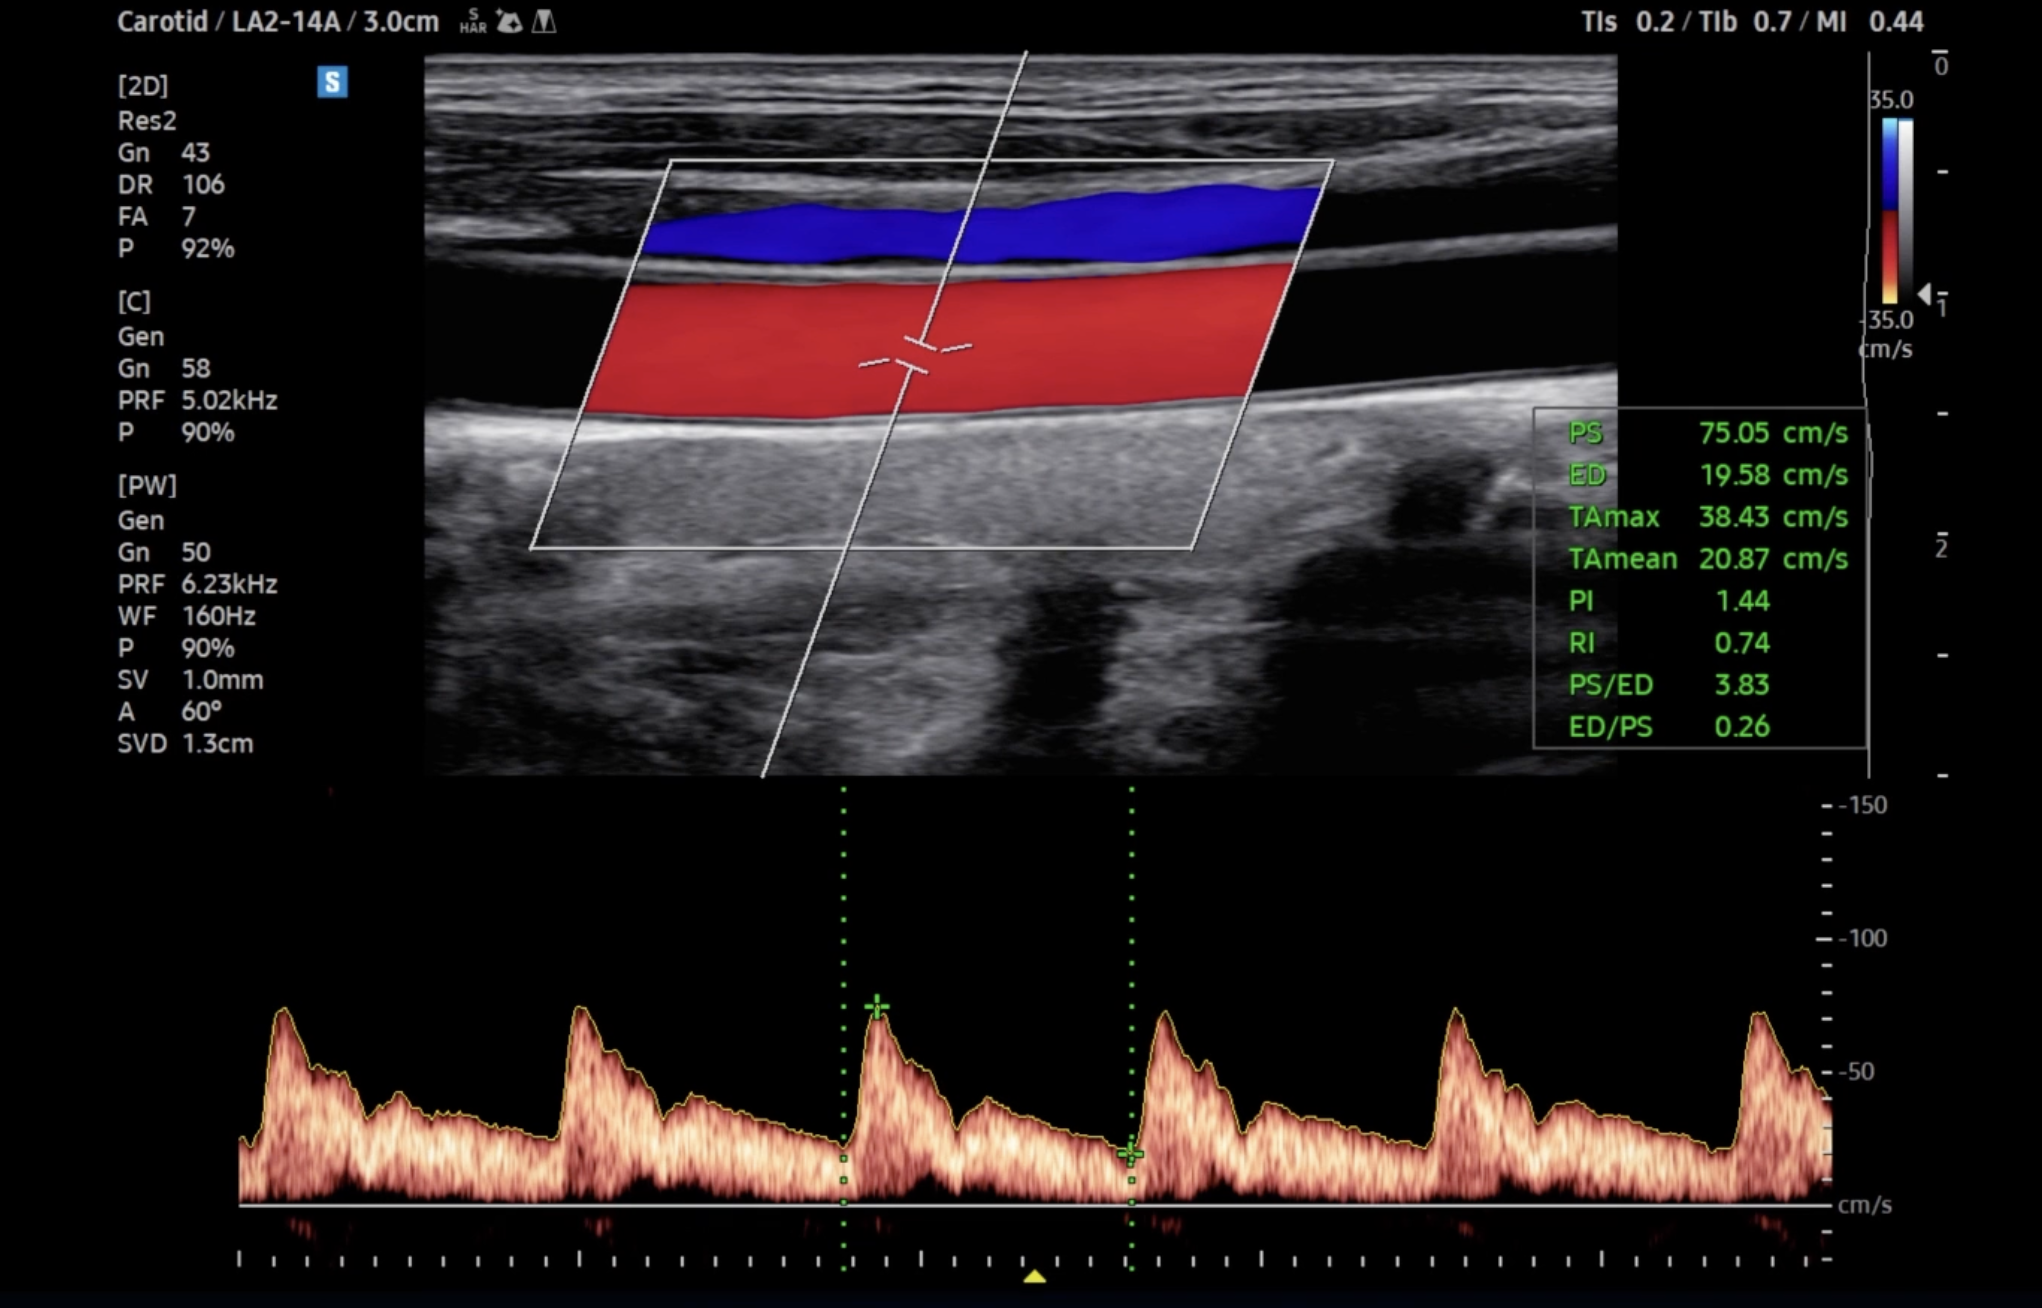

Technische Ausstattung

Entsprechend den Anforderungen unseres breiten Schwerpunktes verfügen wir über alle diagnostischen Möglichkeiten der konservativen Medizin und Diagnostik

Technik

Es ist unsere Grundüberzeugung, daß Technik dem Menschen folgt und und nicht umgekehrt.

Alle technischen Untersuchungen sind Bestätigungsuntersuchungen im Gespräch und der körperlichen Untersuchung erhobener Befunde.

Diese Grundphilsophie stellt sehr hohe Anforderungen an die Hardware. Wir verwenden nur Hardware der renomiertesten Hersteller aus der Schweiz, den USA und Japan.